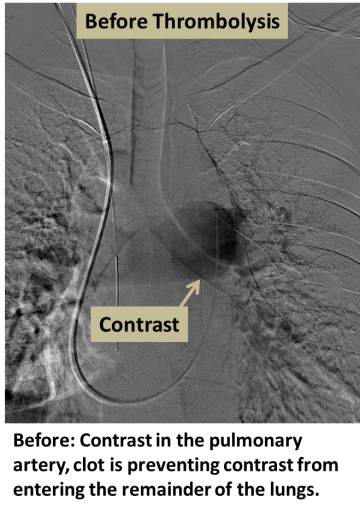

An artery, usually the femoral artery, is accessed with a small puncture, and X-rays are used to navigate a catheter into the occluded artery. A specialized infusion catheter is positioned within or across the clot, and a powerful clot-busting medication (thrombolysis) is dripped into the clot to dissolve it. Follow-up angiography is typically performed in 12-24 hours to determine the success of thrombolysis.